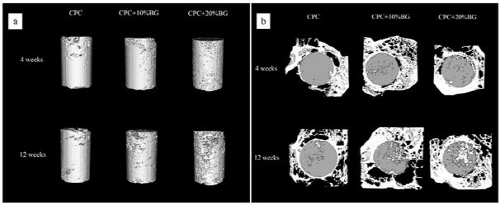

그림 2. Micro-CT를 이용하여 촬영한 injectable 칼슘포스페이트 시멘트의 골 형성 분석[5]